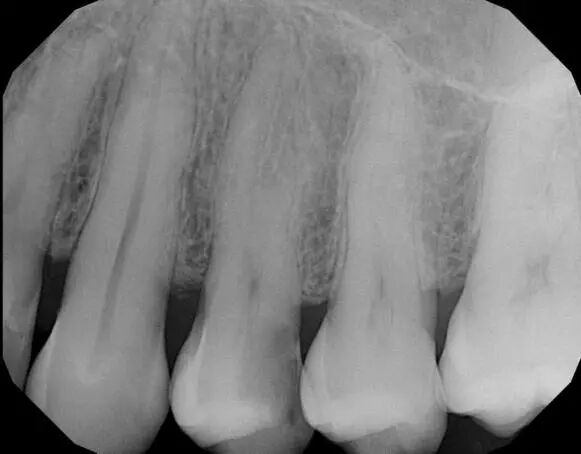

根管充填,尤其是复杂和弯曲根管,医生一般采取冷侧方加压充填,要花30-40分钟才可以完成,而且往往不可避免的会产生一些间隙、气泡、以及侧枝根管充填不密实的现象,同时工作过程中所需要的糊剂过多,侧压时可能导致根折。

热凝牙胶根管充填技术是利用牙胶加热软化后具有流动性的特点,实现了根管的三维充填,使根管充填的效果更理想。它是目前国际认可的最佳根管治疗充填技术。

三是封闭性好,尤其适用于狭窄弯曲和形态复杂的根管治疗,防止再次感染;